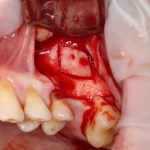

Кстати, обрати внимание на ширину альвеолярного гребня (левая картинка). Она чуть меньше 3 мм. Это объясняет, почему я засомневался в возможности установки имплантатов одновременно с остеопластикой. Понятно и без КЛКТ.

Наперво, мне нужно удалить разрушенный зуб и получить костный аутотрансплантат.

Для получения костного блока, мы открываем донорскую зону, наружную косую линию нижней челюсти.